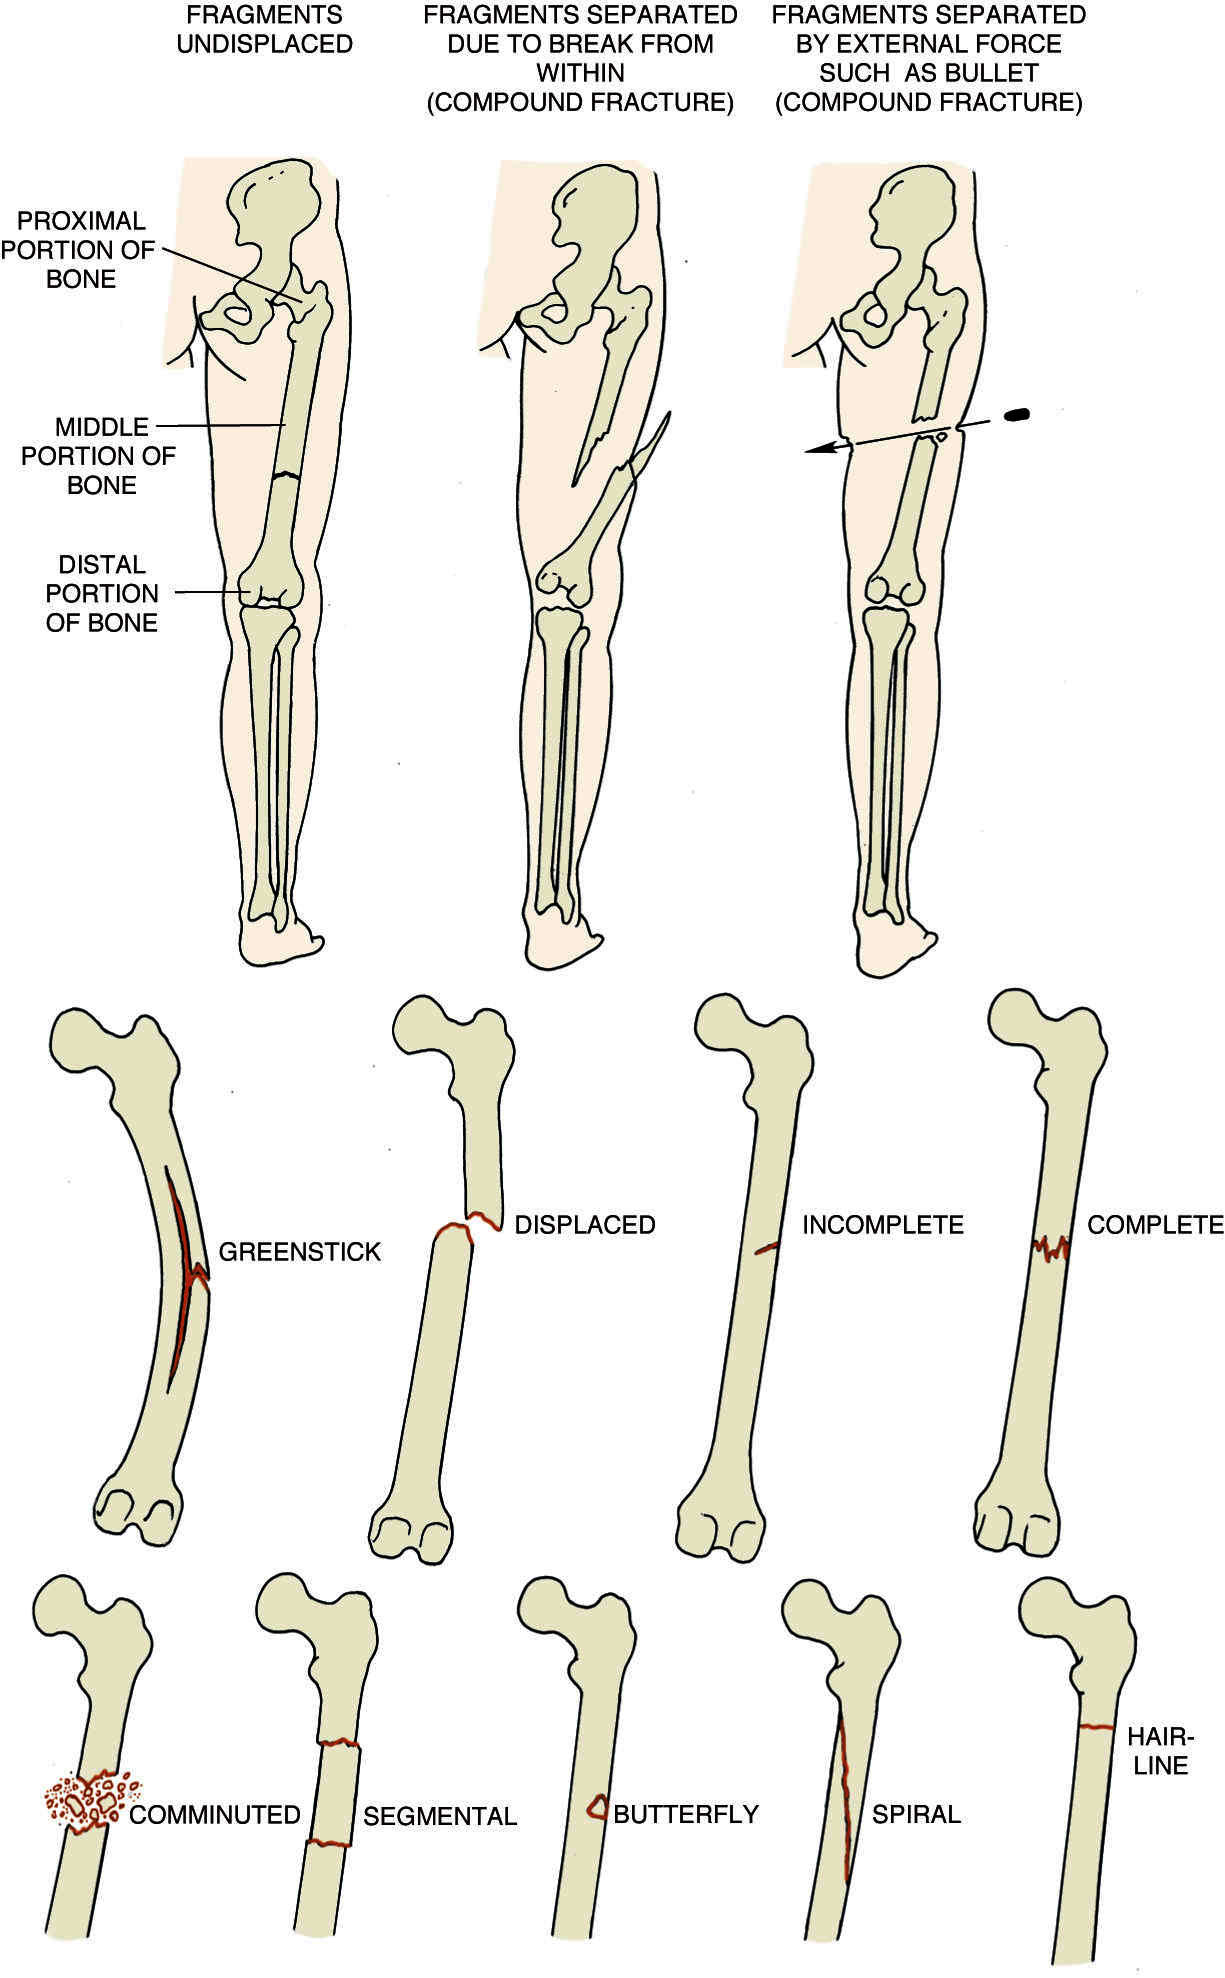

Comminuted Fracture:

A fracture in which the bone is broken or splintered into pieces.

Complete Fracture:

A fracture in which the bone is completely broken (i.e., neither fragment is connected to the other).

Compound Fracture:

A fracture in which fragments of bone protrude through the skin or in which there is a break in the skin or soft tissue at the fracture site. Such a fracture exposes the wound to possible infection.

SYN: SEE: open fracture

Greenstick Fracture:

A fracture in which the bone is partially bent and partially broken, as when a green stick breaks. It occurs in children, esp. those with rickets. There is a compression fracture on the concave side of the bend and a tension fracture on the convex side.

Hairline Fracture:

A minor fracture in which all the portions of the bone are in perfect alignment. The fracture is seen on a radiograph as a very thin line lying between the two segments and not extending through the bone.

Incomplete Fracture:

A fracture in which the line of fracture does not transverse the bone.

Spiral Fracture:

A fracture that follows a helical line along and around the course of a long bone.

Stellate Fracture:

A fracture with numerous fissures radiating from the central point of injury.